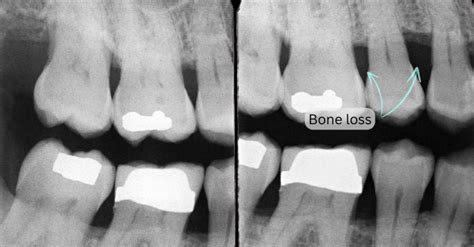

Katherine Wolfe Blog